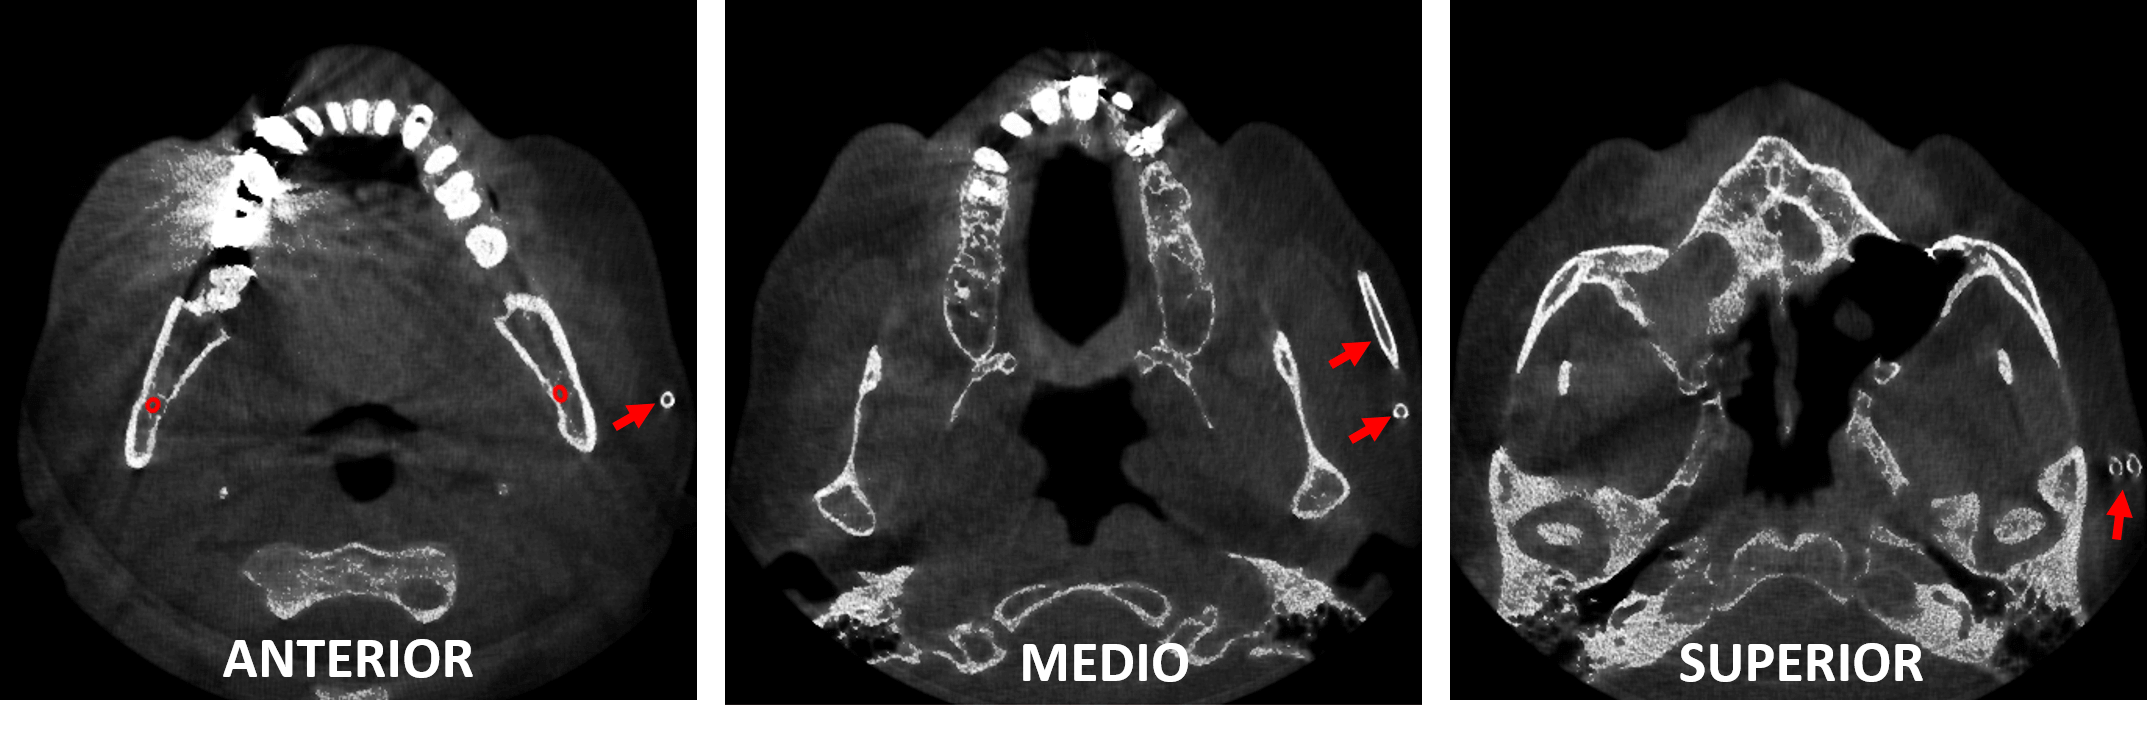

Fig.2

En cortes coronales del lado derecho (Fig.2) se observa el objeto descrito anteriormente (Flechas rojas), donde se aprecia la bifurcación del mismo a nivel más superior.